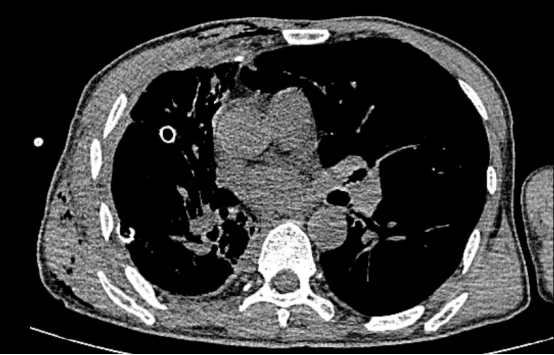

术后影像

术后,患者转入重症一科,在孙万里副主任医师的精细化治疗与护理下,患者接连闯过感染、出血、呼吸功能支持等重重难关。4天后病情趋于稳定,转回胸外二科继续康复。在医护人员的悉心照料下,患者康复出院。